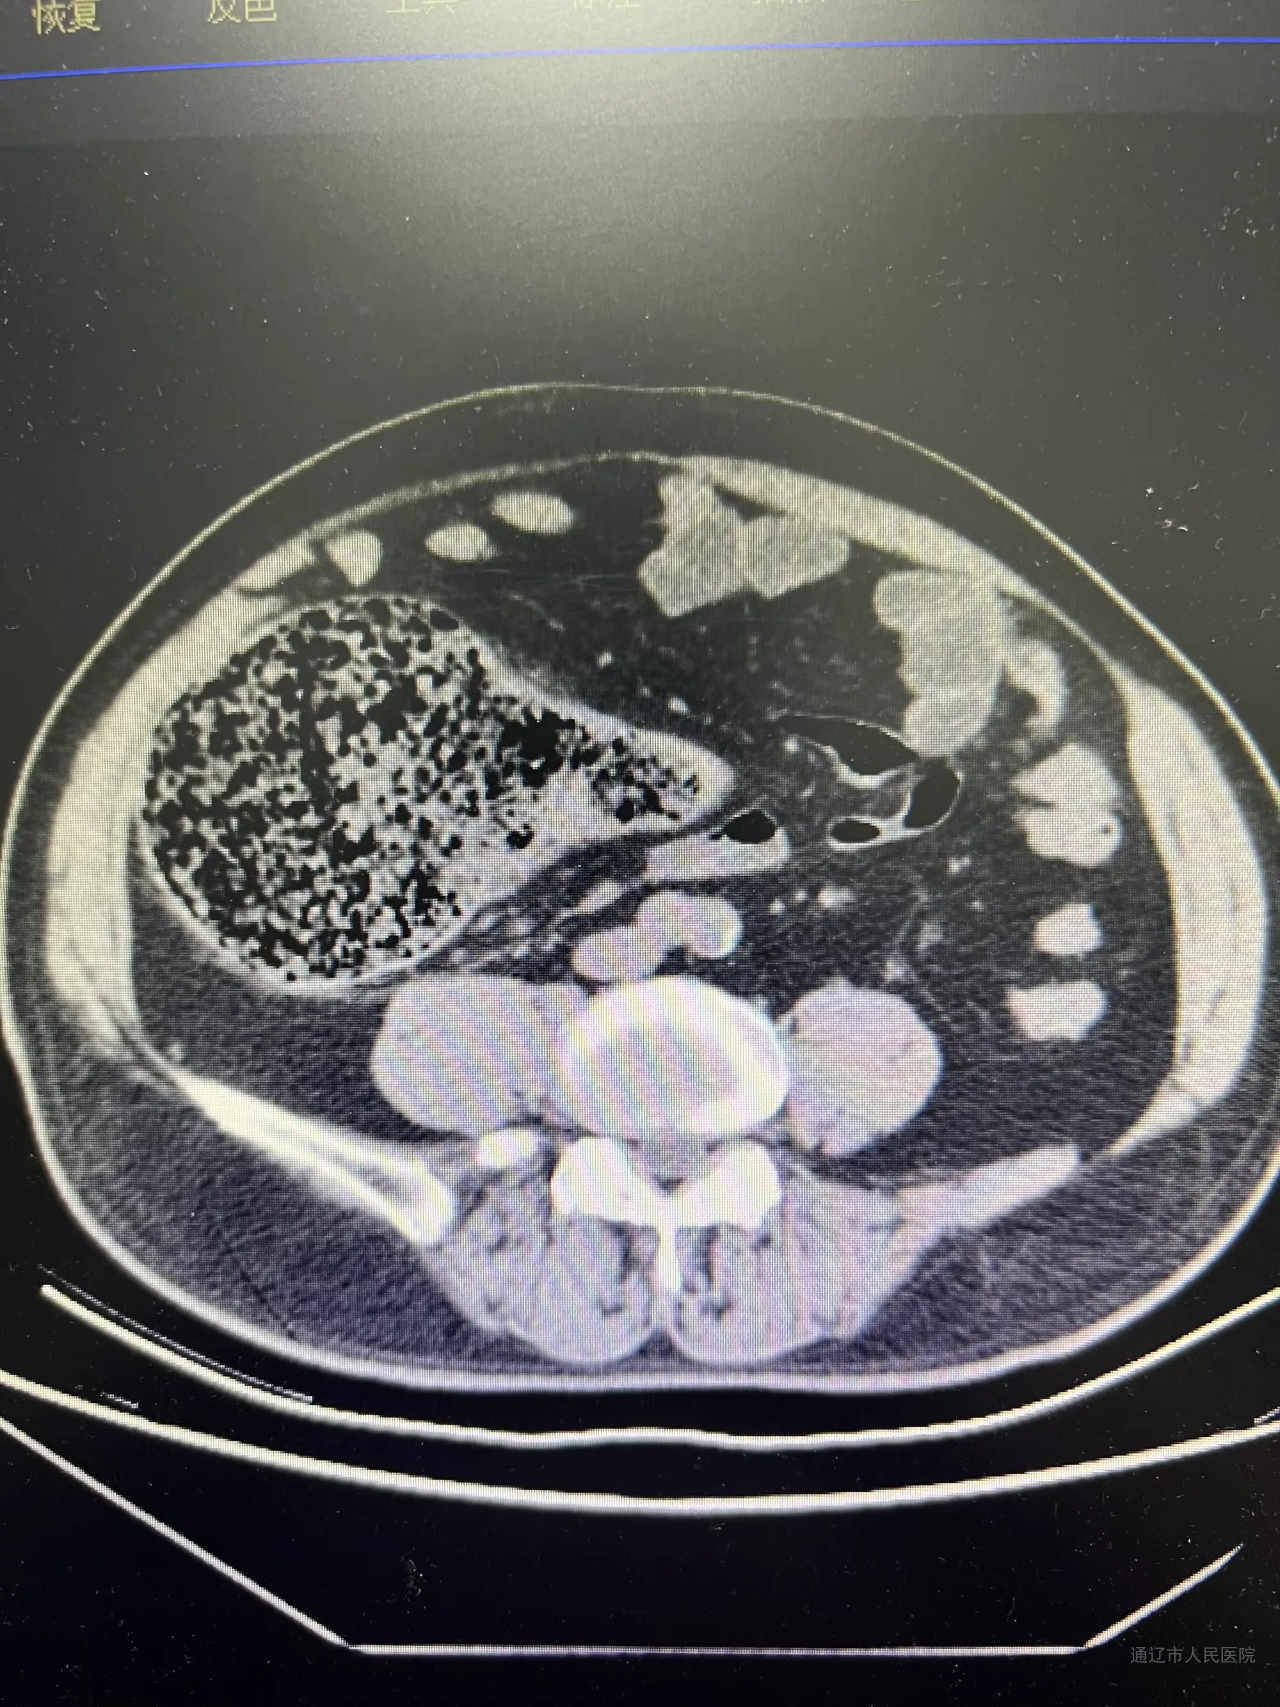

患者为63岁男性,因“间断腹痛、伴排气排便减少1天”就诊于消化内科,经治疗症状未缓解且逐渐加重。会诊后转入胃肠疝外科,腹部CT检查显示升结肠肠壁增厚,考虑恶性病变。鉴于患者腹胀明显,科室迅速完善术前准备,当日在急诊全麻下行回盲部造口术,术后患者状态明显好转。1周后,在全麻下行腹腔镜右半结肠癌根治术,手术由副院长张国友主刀,主任医师郭云峰、副主任医师刘宗旭协助完成,手术经过顺利。

梗阻前CT